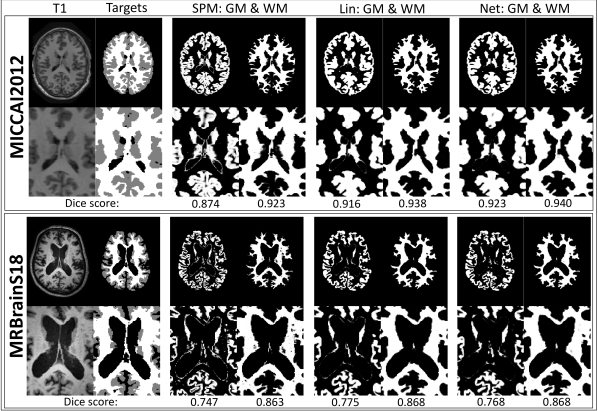

All T1-weighted MR scans were segmented with the algorithm implemented in the SPM12 software444www.fil.ion.ucl.ac.uk/spm/software/spm12, which is based on the generative model described in [3]. In this model, the distribution over categorical labels is independent across voxels, non-stationary, and encoded by a probabilistic atlas deformed towards each subject. The algorithm generates soft segmentations, that is, parameters of the posterior categorical distribution over labels. We pulled the GM, WM and OTHER classes from these segmentations. Fig. 3 shows the T1-weighted image of one subject from each dataset, with its corresponding target labels and SPM12 segmentations555Besides disabling the final MRF clean-up, we used the default parameters of SPM12..

Refer to caption

Figure 3: Example training data and results. From left to right: T1-weighted MR image with target labels, SPM GM and WM segmentations, results of applying the linear MRF model to the SPM segmentations, results of applying the nonlinear MRF model to the SPM segmentations. Below each tissue class are the corresponding Dice scores, computed with the target labels as reference.

The 10-fold cross validation results in Fig. 4a show that the increase in Dice scores for both GM and WM is statistically significant after applying either of our two MRF CNN models. (Fig. 3 shows the results for a randomly selected MICCAI2012 subject). With a mean Dice of {GM=0.867,WM=0.921}formulae-sequenceGM0.867WM0.921\{\text{GM}=0.867,\text{WM}=0.921\} for SPM12, and {GM=0.901,WM=0.929}formulae-sequenceGM0.901WM0.929\{\text{GM}=0.901,\text{WM}=0.929\} and {GM=0.909,WM=0.931}formulae-sequenceGM0.909WM0.931\{\text{GM}=0.909,\text{WM}=0.931\} after applying the linear and nonlinear MRF, respectively. The results imply that the classical generative approach of SPM12, which currently ranks in the top 50 on the MRBrainS13 challenge website666mrbrains13.isi.uu.nl/results.php, could move up quite a few positions by application of our proposed model trained on the challenge data. As can be seen in Fig. 4a, for one of the subjects, all models perform substantially worse. On closer inspection, this subject suffers from major white matter hyper-intensities. This abnormality is currently not handled well by the MRF CNN models, which obtain lower Dice scores than the initial SPM12 segmentations.

Fig. 4b shows results when applying the models to data from a different centre, not part of the training data (Fig. 3 shows the results for a randomly selected MRBrainS18 subject). Mean Dice scores are {GM=0.722,WM=0.816}formulae-sequenceGM0.722WM0.816\{\text{GM}=0.722,\text{WM}=0.816\} for SPM12, and {GM=0.761,WM=0.831}formulae-sequenceGM0.761WM0.831\{\text{GM}=0.761,\text{WM}=0.831\} and {GM=0.755,WM=0.829}formulae-sequenceGM0.755WM0.829\{\text{GM}=0.755,\text{WM}=0.829\} after application of the linear and nonlinear MRF, respectively. Application of the MRF improves both GM and WM segmentations. The nonlinear MRF performs slightly worse than the linear version. This result could be due to the nonlinear model – which possesses many more parameters than the linear model – overfitting to the training subjects of MICCAI2012. Additionally, the nonlinear MRF may struggle with the MRBrainS18 subjects that have pathology (e.g. white matter hyperintensities). Still, the fact that Dice scores improve when applying the model to new data shows that we can successfully improve segmenting images from different MR imaging protocols.